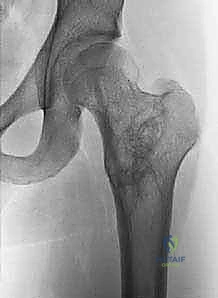

تُظهر هذه الأشعة السينية (X-ray) كيس عظم أحادي الغرفة (UBC) في الجزء العلوي من عظم العضد. لاحظ كيف أن الكيس يسبب ترققاً في قشرة العظم دون أن يخترقها.

* المواقع الشائعة: الجزء القريب من عظم العضد (الكتف) والجزء القريب من عظم الفخذ (الورك) يمثلان حوالي 40% إلى 80% من الحالات.

* النشاط: يُصنف إلى "نشط" إذا كان ملامساً لصفيحة النمو (مما قد يهدد نمو العظم)، أو "كامن" إذا ابتعد عن صفيحة النمو مع استطالة العظم. الجدار المبطن لهذا الكيس عبارة عن غشاء ليفي رقيق جداً.

- في الـ UBC، تظهر الآفة كمنطقة شفافة (سوداء) مركزية داخل العظم. وهناك علامة مميزة تُسمى "علامة الورقة المتساقطة" (Fallen Leaf Sign)، حيث تسقط قطعة صغيرة من قشرة العظم المكسورة داخل الكيس المملوء بالسائل، وهي علامة مؤكدة بنسبة 100% تقريباً على الـ UBC.